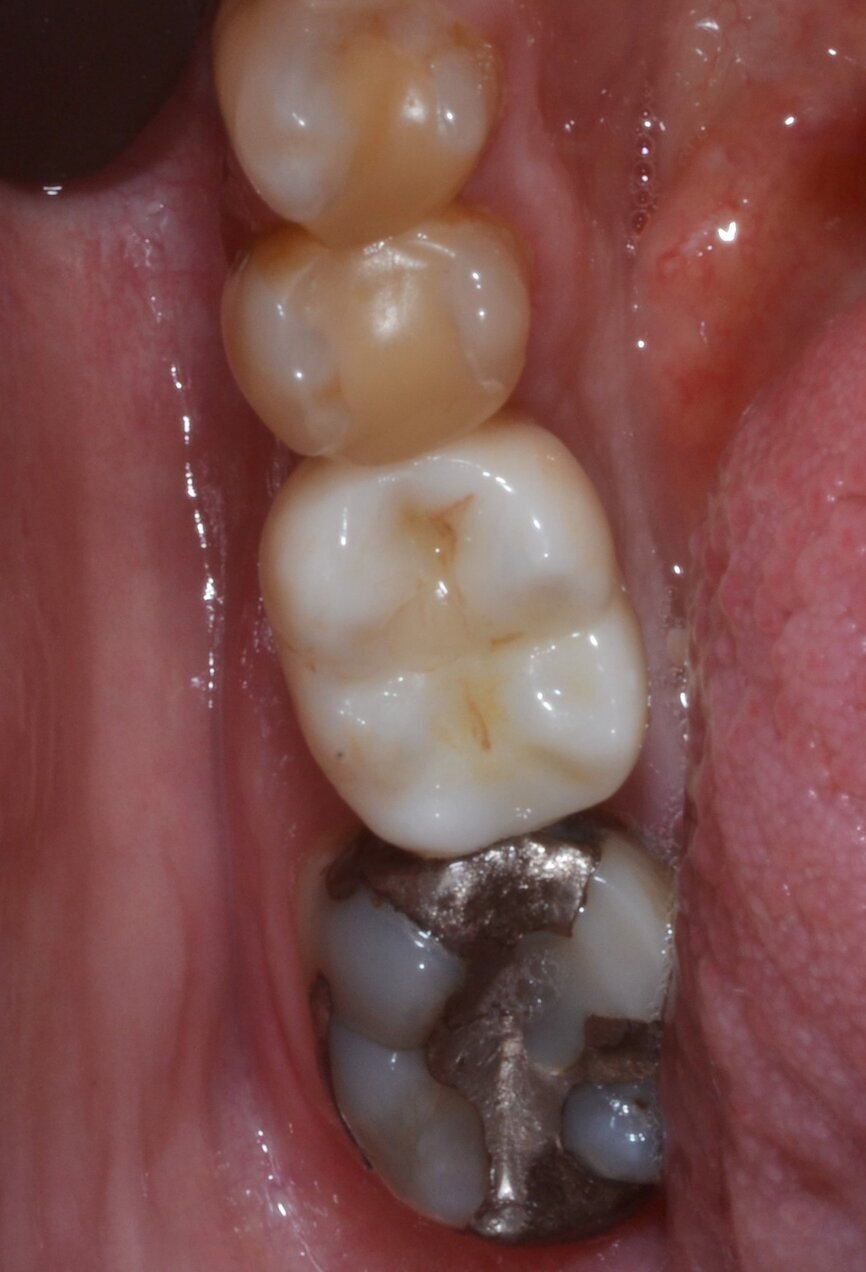

After 12 weeks, Salvesen removed the temporary crown, revealing that the soft tissue had healed very well (Fig. 15). He then began the digital workflow. For the final crown, a digital impression was taken with a 3Shape intra-oral scanner, using a Straumann CARES scan body. A monolithic zirconia crown was then seated passively on to the implant in a healed and preconditioned soft-tissue environment (Figs. 16–19).

Fig. 18: Final crown in position, lateral view.

Fig. 20: One-year follow-up occlusal view.

Fig. 21: One-year follow-up lateral view.